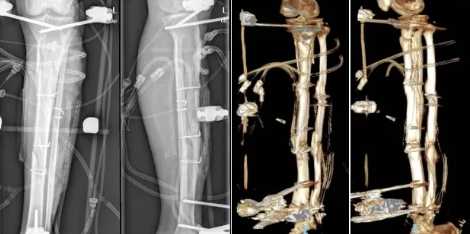

男患者郑某某,58岁,因“左小腿重物砸伤致肿痛、流血3周”入住我院创伤骨科病区,入院前于当地医院急诊行“左小腿清创、胫腓骨切开复位、钢丝捆绑固定、外固定支架固定、VSD术”。

入院后完善相关检查,并作好术前准备,分次行“左下肢清创、负压引流术”,术后软组织感染、坏死明显改善,但残留大段胫骨裸露、坏死(约22cm),怎样彻底清除坏死、感染骨段,修复创面和重建骨缺损是该患者治疗的关键和难点。

经过创伤骨科与整形外科梁杰主任、莫自增医师团队进行沟通后,行“左胫骨坏死骨清除、Masquelet 技术分期治疗骨缺损”,并联合整形科医师团队一期实施了“股前外侧游离皮瓣修复术+游离皮片移植术”修复创面,术后患者皮瓣和皮片成活良好,皮肤软组织愈合,感染明显好转后出院。